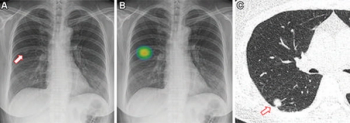

Emerging research suggests that adjunctive artificial intelligence (AI) improves sensitivity for a variety of abnormalities on chest X-rays regardless of radiologist experience level, including an average 26 percent increase in sensitivity for pneumothorax.

BraveCX, an artificial intelligence (AI)-enabled software, reportedly has an area under the curve (AUC) of 98 percent for detecting pneumothorax on chest X-rays.

Artificial intelligence (AI) assessments of chest X-rays identified 28 percent of a 17,000 plus cohort of never-smokers as being at high-risk for lung cancer, according to research to be presented at the annual Radiological Society of North America (RSNA) conference next week.